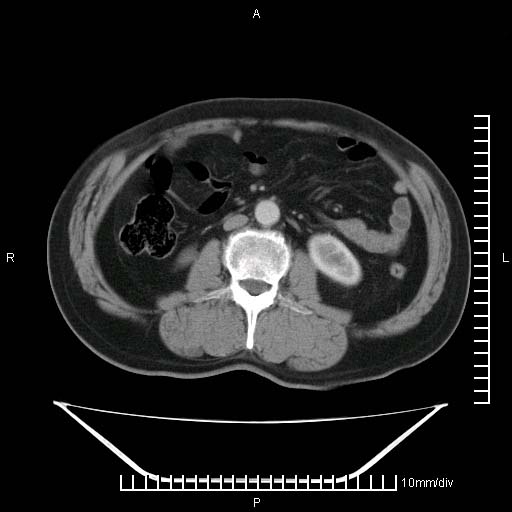

标题: CT25082:肝脏增强:男性,70岁 [打印本页]

标题: CT25082:肝脏增强:男性,70岁

患者以心脏疾病收住院,腹部无明显症状,b超查肝脏有占位。

牛眼征,中心坏死无强化,外缘强化,最外缘又见低密度,考虑转移,与脓肿鉴别

肝内多发转移瘤,右下肺炎症并少量胸水。胃壁增厚建议胃镜,胰尾部“病变”为肠管。

1)肝脏多发性转移瘤(不排除胰尾癌转移所致可能)。2)腹水。3)右侧少量胸腔积液。

ct25082 结果:转移瘤

外院mr结果:胰尾恶性占位。